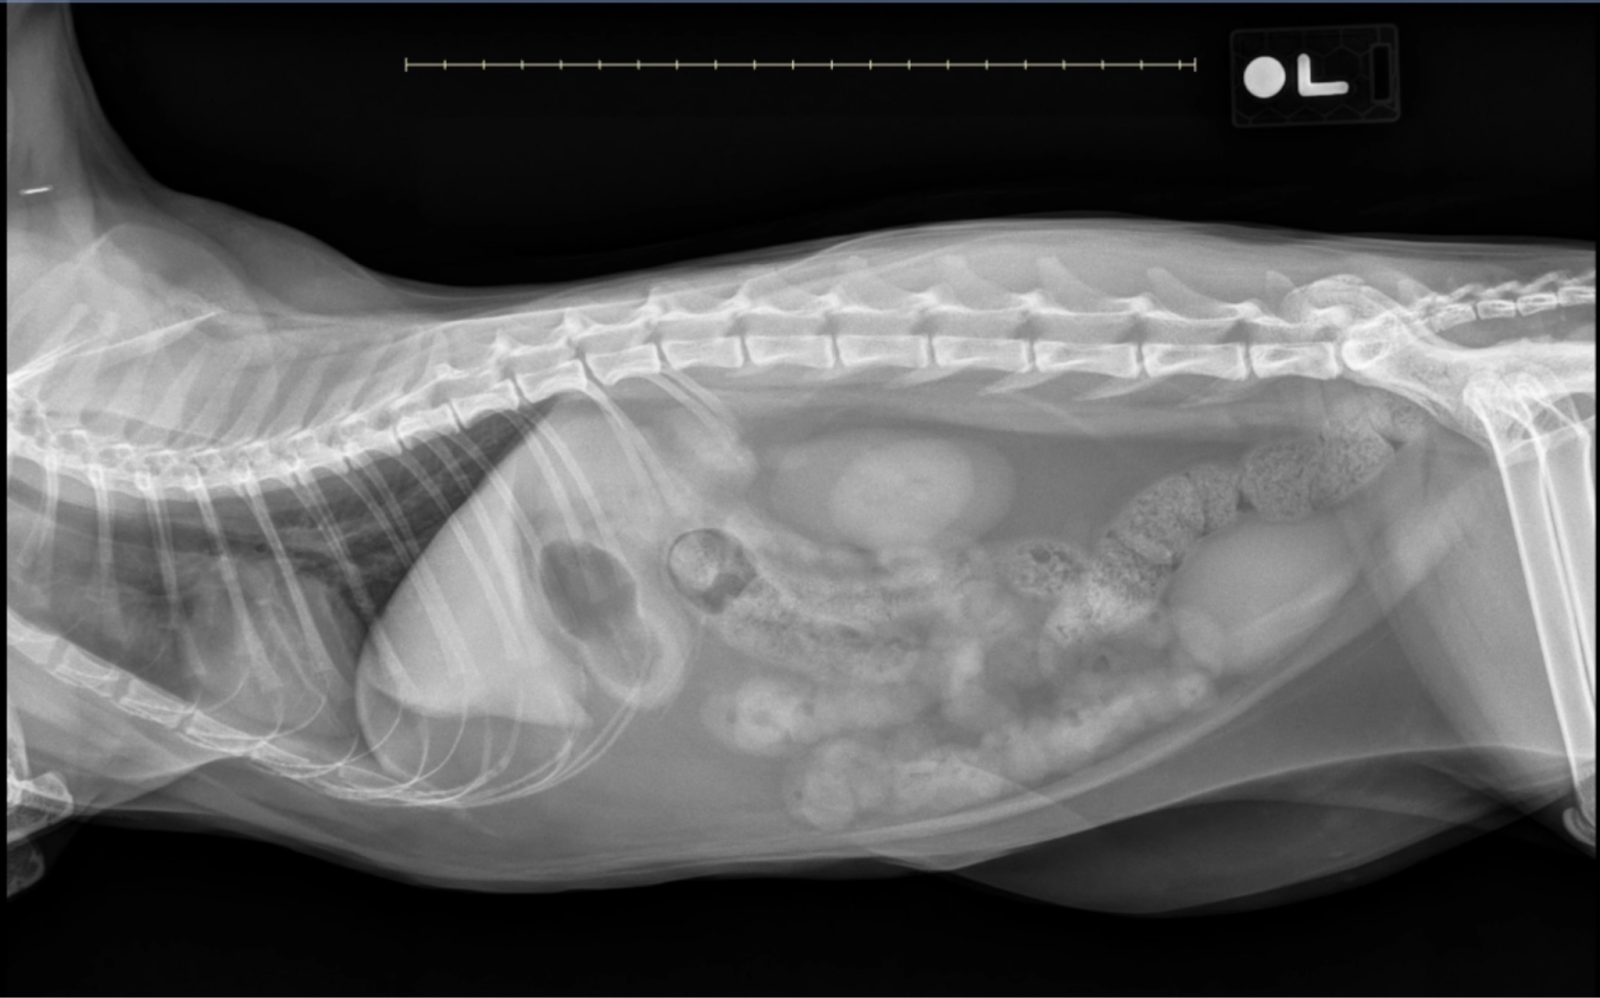

Left lateral abdominal x-ray of a cat with small intestinal plication and fragmented intraluminal gas, classic signs of linear foreign body obstruction.

Image 1: Left Lateral View

• Stomach: Mildly gas and fluid-filled, slightly more than typical in a feline stomach.

• Pylorus: Appears normally gas-filled without visible foreign material, suggesting that any anchor point is distal to the stomach.

• Small Intestine: Extensive plication throughout the abdominal cavity with serpentine and bunching patterns, indicating a linear foreign body obstruction (LFBO).

• Colon: Moderately filled with formed fecal material; although this may seem inconsistent with obstruction, it is not uncommon in feline LFBO cases due to gastrocolic reflexes.